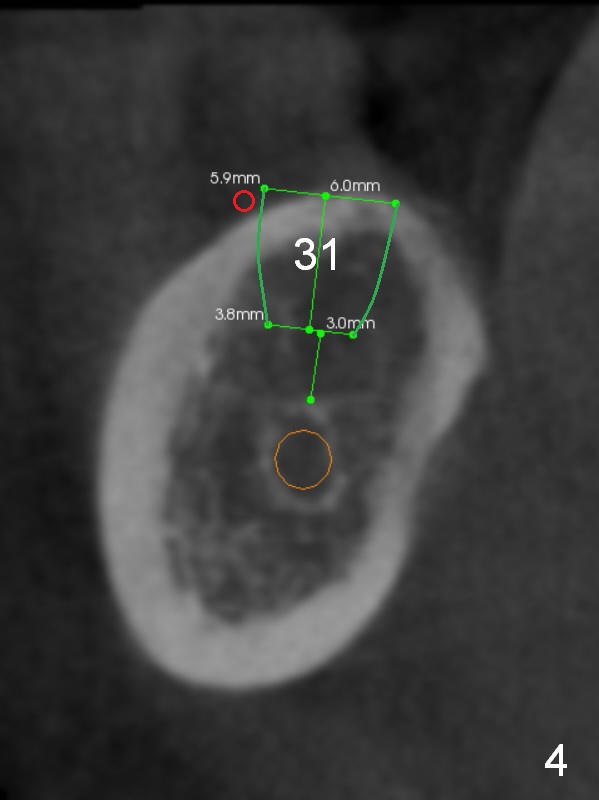

Fig.2 (sagitttal section) shows that the bone height at the site of #31 is shorter than that of #30. There is a 1 mm separation from the Inferior Alveolar Nerve (brown) if a 8 mm implant is placed at #31 (Fig.2,3 (coronal section)), whereas 3 mm separation for a 6 mm implant (Fig.4). Since the tooth #2 is supraerupted, the shorter implant at #31 is more appropriate. It is placed a little deeper (Fig.4' arrow) so that the abutment or the opposing tooth does not need to be trimmed too much. In addition, choose a widest abutment (purple, e.g., 7.8 mm) with the shortest cuff (pink, 1 mm). A splinted immediate provisional will be fabricated to prevent the gingiva from growing into the abutment margin. At restorative phase, a smaller abutment will be used (e.g., 5.8 mm) so that the gingiva is clear from the margin. It will be easy for impression. Then the provisional will be relined to keep the gingiva from growing into the space just created by changing abutments. Bone graft will be needed buccal to the implant at #31 (Fig.3,4 red circle; L: lingual).

A coronal section at the site of #30 confirms that a 12 mm implant is safe (Fig.5).

Initial height at #30 and 31 will be 12 and 8 mm after infiltration anesthesia. Osteotomy at #31 is proceeded cautiously. If the 1st intraop PA confirms depth safety margin, depth will be 2 mm more than implant length so that the implant will be placed lower.